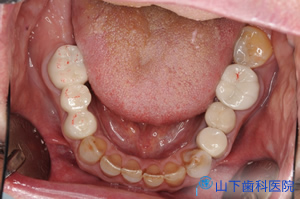

| 初診時のレントゲン写真です。 | ![]() |

| 上下の奥歯が咬み合うことで決まる咬合が不安定で、下の前歯が上の前歯を突き上げています。 予知性がない右下、左上の4番目を抜歯して落ち着いた状態です。 |

| 5年経過後のレントゲン写真です。 | ![]() |